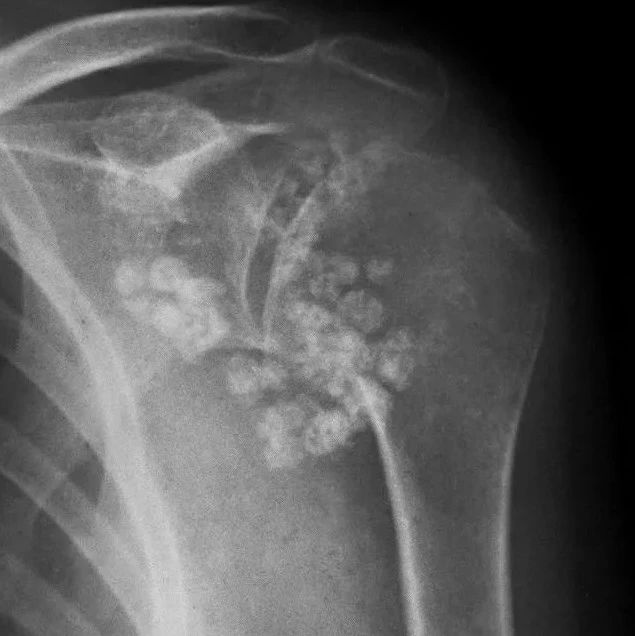

音频课程2022 · Audio Course陈飞雁复旦大学附属华山医院骨科点击收听✦学习笔记滑膜软骨瘤病(Synovial chondromatosis SC)是种相对罕见的关节滑膜或滑膜囊、腱鞘发生异常增殖的疾病。最早称为Reichel’s综合征,1958年Jaffe将本病命名为“滑膜软骨瘤病”。本病最常发生在膝关节,其次可影响髋关节、肘关节、踝关节、颞下颌关节和肩关节等部位。以滑膜形成软骨结节为特征,可带蒂生长,亦可能脱落到关节腔形成游离体(关节鼠),后期可发生钙化或骨化。...

滑膜软骨瘤病又称为滑膜骨软骨瘤病,是一种少见的、良性的发生于关节滑膜组织、关节周围滑囊及腱鞘的软骨增生性病变,多为滑膜的良性增生及化生,并产生多个关节